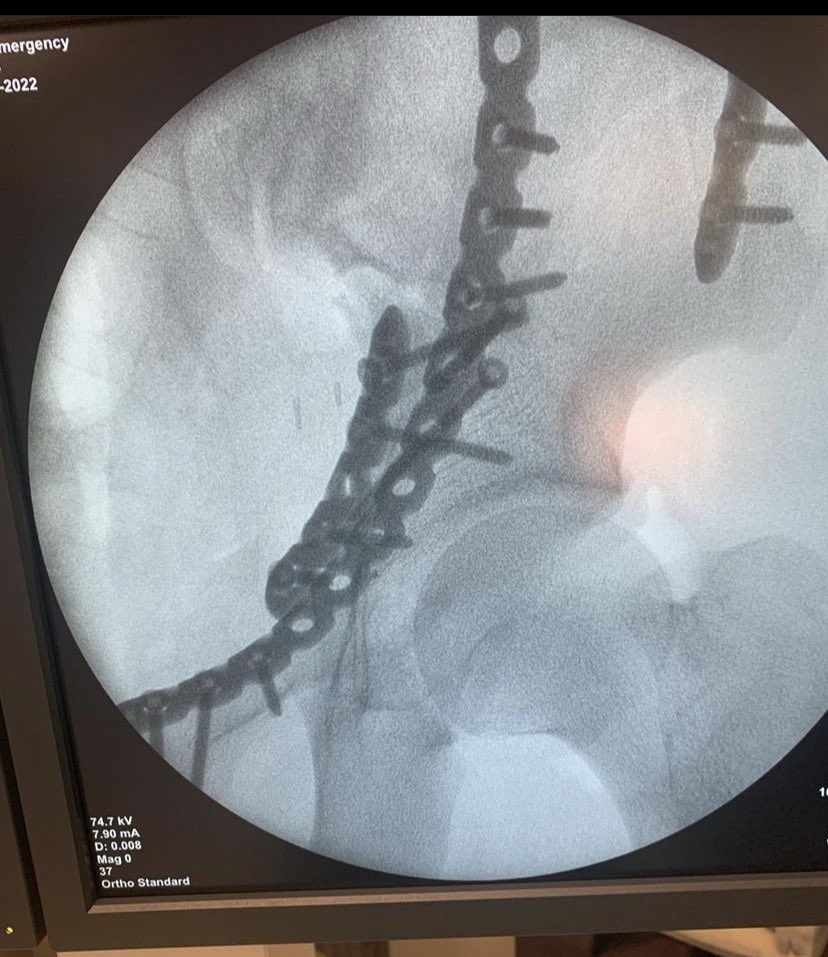

47 years old male patient, neglected (3 mounths) multilevel thoracolumbar junction spine fracture (L1, T12 and endplate of T11). there is monosegmental pure osseous failure of the posterior tension band in T12. this also called "Chance" fractures. #spinesurgery #spine